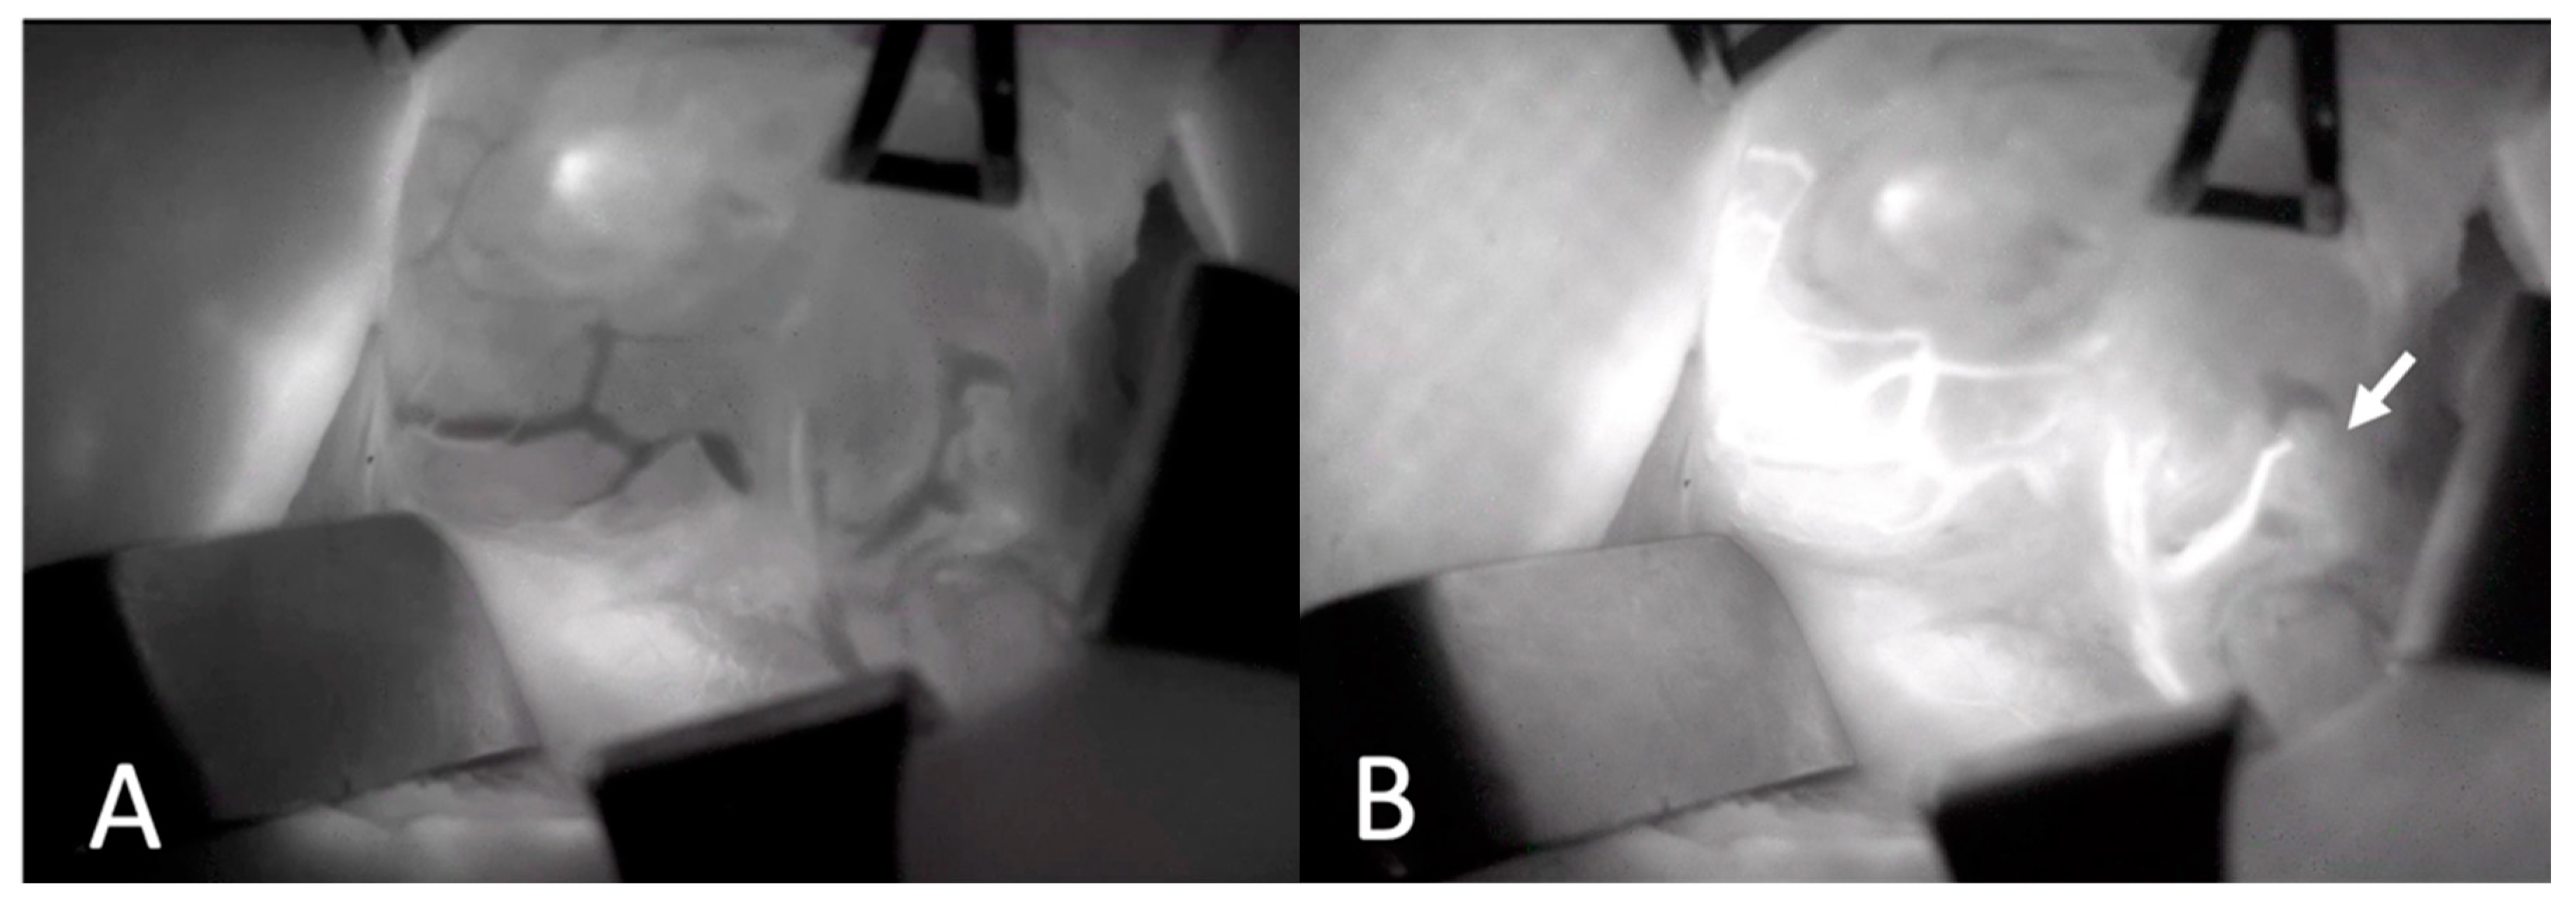

Two experienced board-certified endocrine surgeons performed the operations. For all patients, the conventional subcapsular thyroidectomy approach was used. After a Kocher incision, the subcutaneous tissues and platysma were divided with electrocautery. Subplatysmal flaps were then raised inferiorly extending into the sternal notch and superiorly extending to the thyroid cartilage. The strap muscles were divided and retracted laterally. The right and left thyroid glands were mobilized laterally by blunt dissection and using electrocautery. Retracting the thyroid lobe medially, the middle thyroid vein is identified and ligated. The anterior branches of the superior thyroid artery were dissected and ligated taking care not to harm the external branch of the superior laryngeal nerve. The superior parathyroid gland was then identified by a thorough examination of the superior pole of the thyroid. Then, the inferior parathyroid gland was searched around the inferior pole. Before any dissection, the presumed parathyroid glands were seen with the naked eye. On the opposite side, a similar procedure was used to ensure that as many parathyroid glands as possible could be seen. A solution of ICG (VerdyeTM, Diagnostic Green Ltd., Athlone, Ireland) was created by dissolving 25 mg of powdered ICG in 10 mL of distilled water. For each ICG study, 1 mL of the solution was injected, and the IV line was washed with 10 mL of saline. The vascular supply of the detected parathyroid glands was visualized using SPY-PHI camera (Stryker Corp. Kalamazoo, MI, USA) (Figure 1). All parathyroid glands identified by the SPY-PHI camera were counted and their locations were recorded. The vascular supply of each gland was noted, and dissection was continued accordingly, taking care not to harm any vascular branch supplying parathyroid glands. Thyroidectomy was then completed, and the specimen was removed en-block. An additional 1 mL of ICG was injected and under fluorescence mode, the perfusion of parathyroid glands was visualized (Figure 2). The perfusions of parathyroid glands were compared to the trachea in SPY Fluorescence mode using the fluorescence intensity measurement property. If one gland seemed to be poorly perfused, under direct visualization of the SPY-PHI camera, another 1 mL of dissolved ICG was injected, and the change in fluorescence intensity was inspected in SPY Fluorescence mode. If the gland showed less than 25% increase in fluorescence intensity, the gland was assumed to be nonviable and was excised and autotransplanted. Additionally, the removed thyroidectomy specimen was also imaged using SPY-PHI camera for any parathyroid gland. If found, they were reimplanted.

Figure 2. Intraoperative Images of Left Upper Parathyroid Gland. Fluorescence intensity showing perfusion of parathyroid gland is quantified and compared by contrast angiography (A,B).